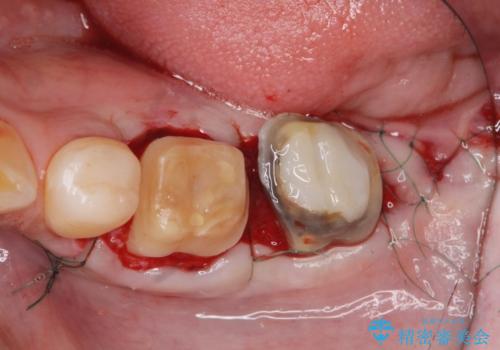

- 著しい歯ぎしりですり減ってしまった、奥歯のクラウンのやりかえを希望され来院されました。

このままの状態でクラウンのやりかえを行うと高さが低く安定の悪いクラウンとなってしまうため、事前に歯周外科手術を行い歯ぐきを下げることで安定性の高いクラウンを製作する治療計画としました。

高さの低いクラウンはセメントが漏出しやすく脱離しやすいだけでなく虫歯の再発の可能性も高まってしまいます。

長期にわたりに安定した環境に整えることで、長く使える可能性を高めることができます。